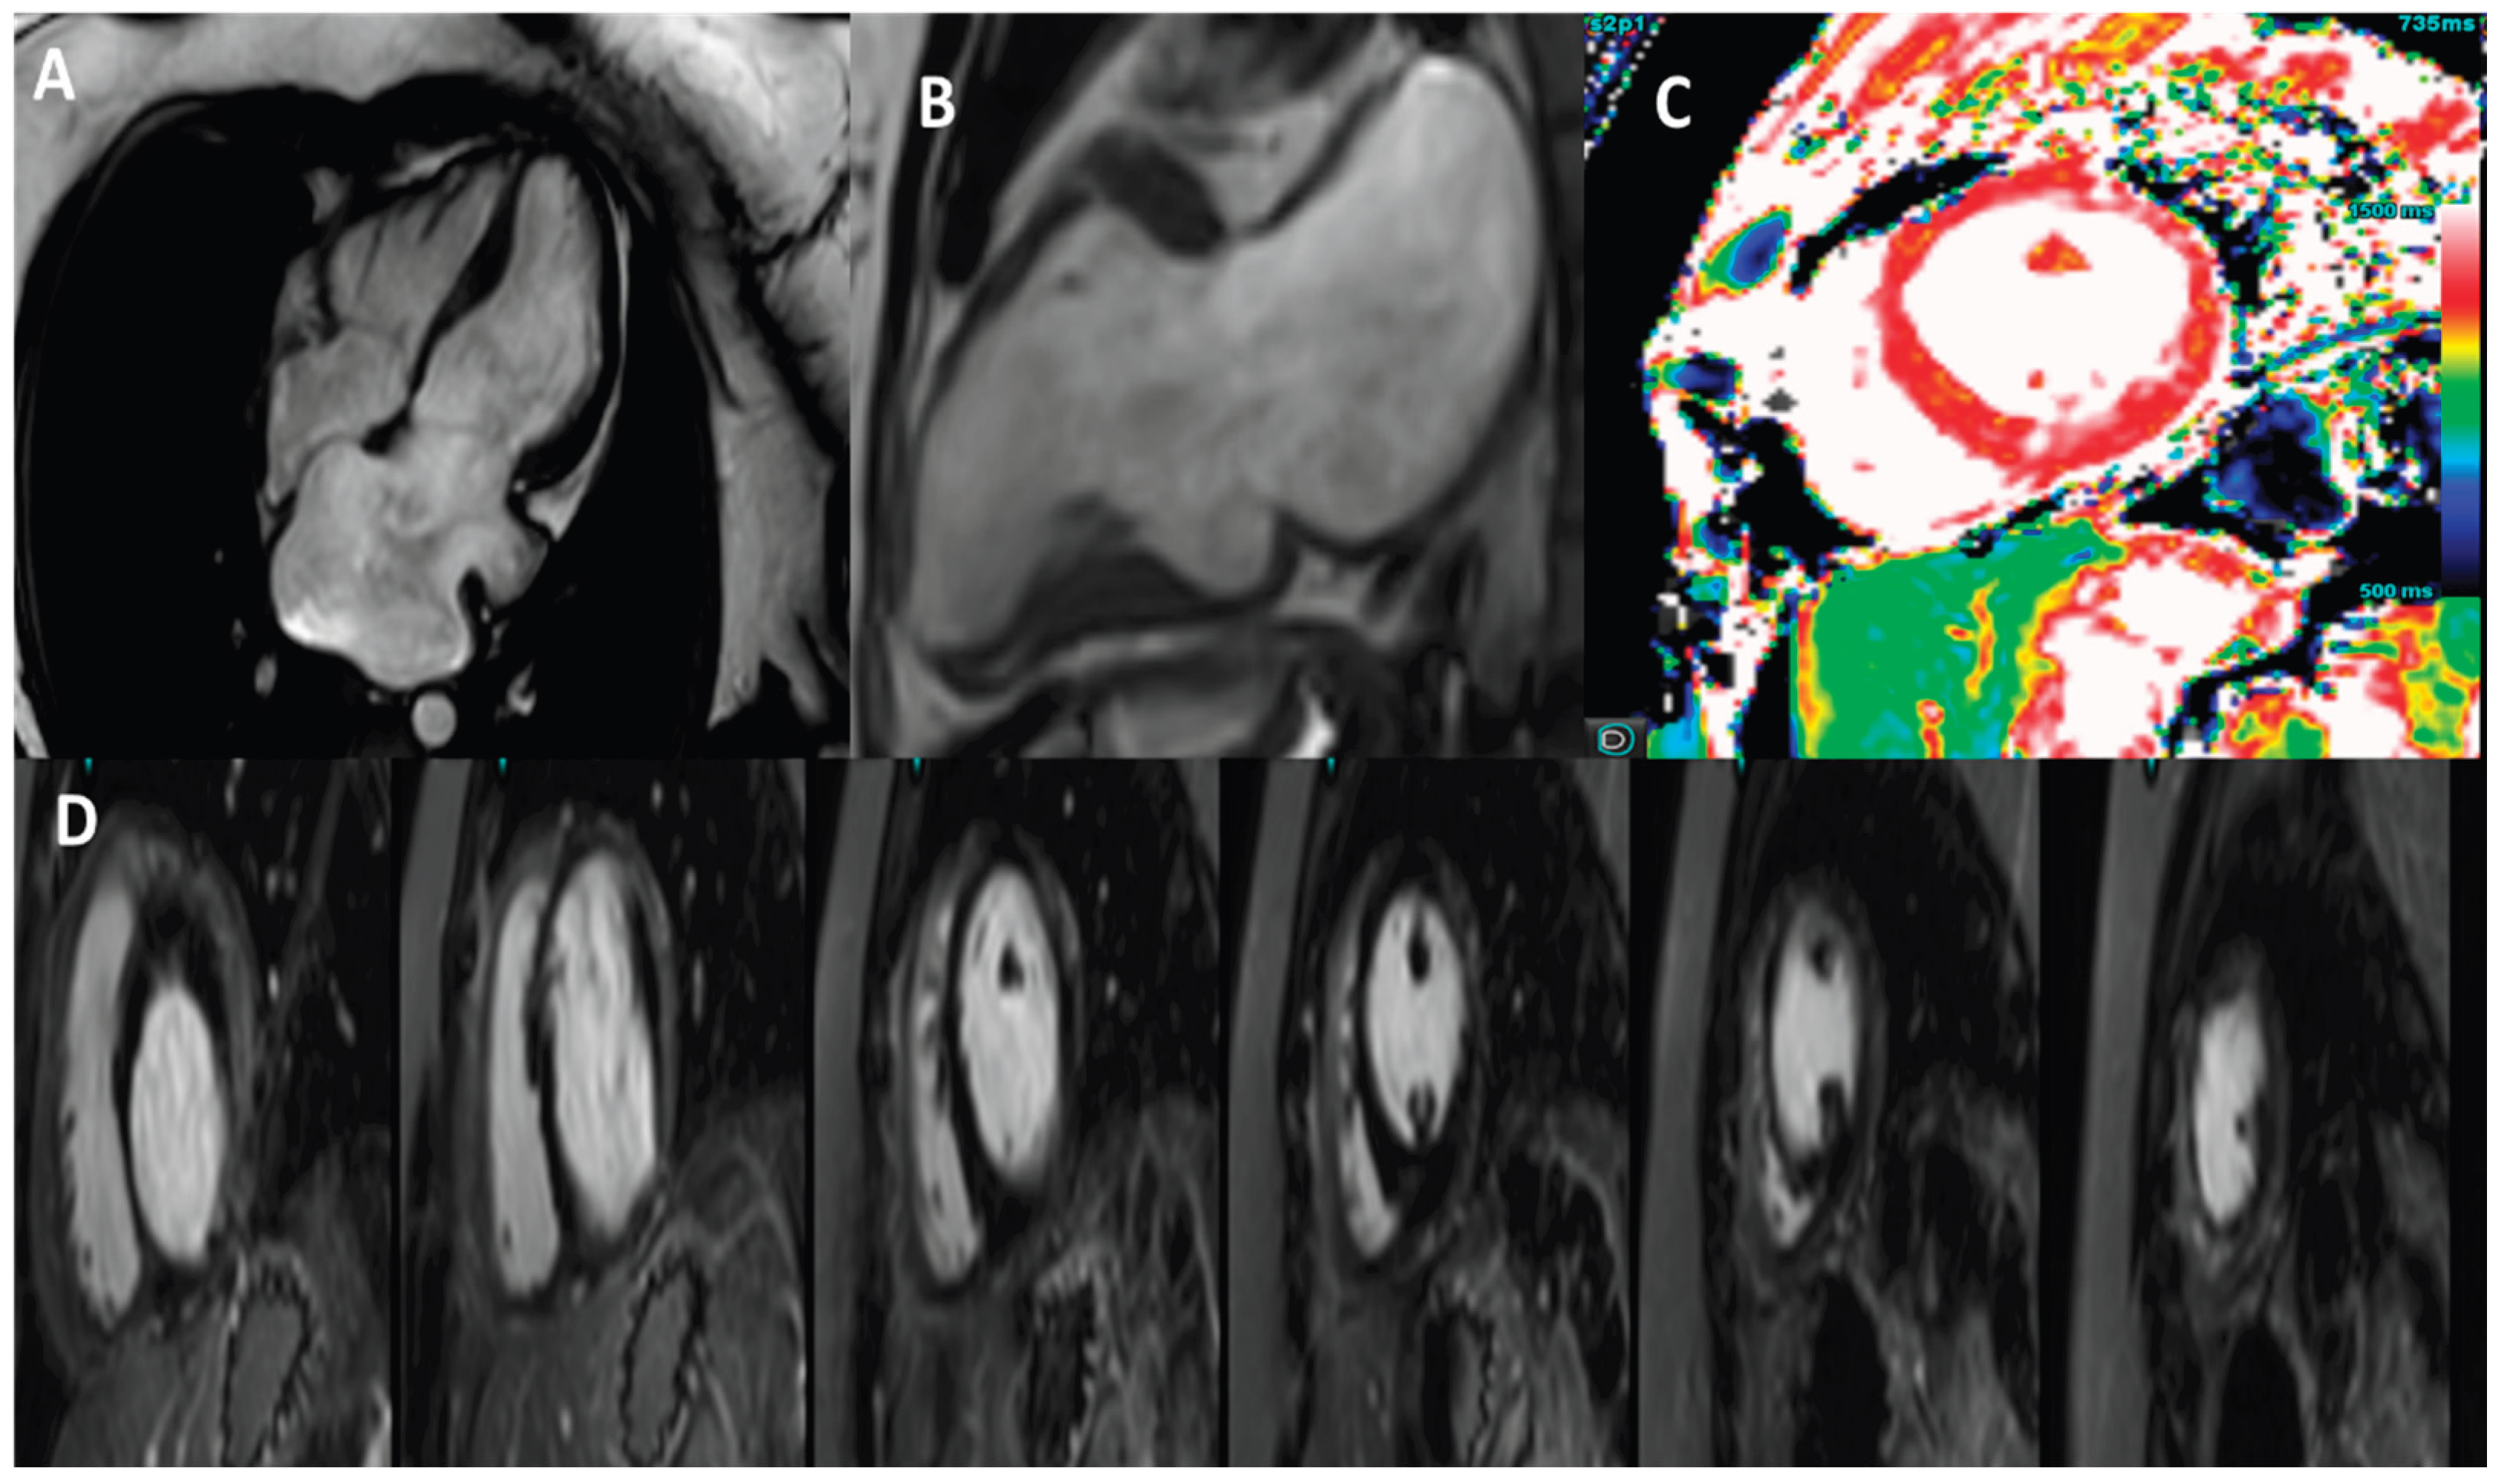

The patient underwent cardiac magnetic resonance imaging, which subsequently revealed left ventricular volumes at the upper limits of normal with preserved systolic function (LVEF = 62%). CMR derived GLS was slightly decreased, –16.6%. IVWT and PWT were 8 mm respectively 9 mm. Moreover, no regional wall motion abnormalities were identified except the presence of a small aneurysmal outpouching in the basal inferior wall.

Native T1 values were mildly elevated, indicating diffuse interstitial myocardial fibrosis, while T2 values were normal, ruling out active myocardial edema. Mild mitral regurgitation was also detected on cine images with severe left atrial dilation. The absence of late gadolinium enhancement and normal T2 values argued against infiltrative or inflammatory cardiomyopathies, supporting a primary genetic etiology. Pericardial thickness was normal and no septal bounce or respiratory interventricular dependence was observed on cine imaging, making constriction unlikely.

Figure 3. 3 Tesla cardiac magnetic resonance images. A) Horizontal long axis view showing the enlarged left atrium. B) Vertical long axis view showing a basal inferior wall aneurysm. C) T1 native mapping with a value of 1260 ms. D) Phase-sensitive inversion recovery (PSIR) showing no LGE enhancement .